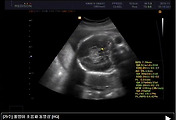

예정일은 1월 26일에 변함은 없습니다.

몸무게가 2.4kg으로 같은 시기의 후니가 2.9kg이었으니 후니 보다 조금 작습니다.

대신 양수는 정상 범위에서 많아 배는 많이 불러보이구요..

그 외 특이사항은 없군요.